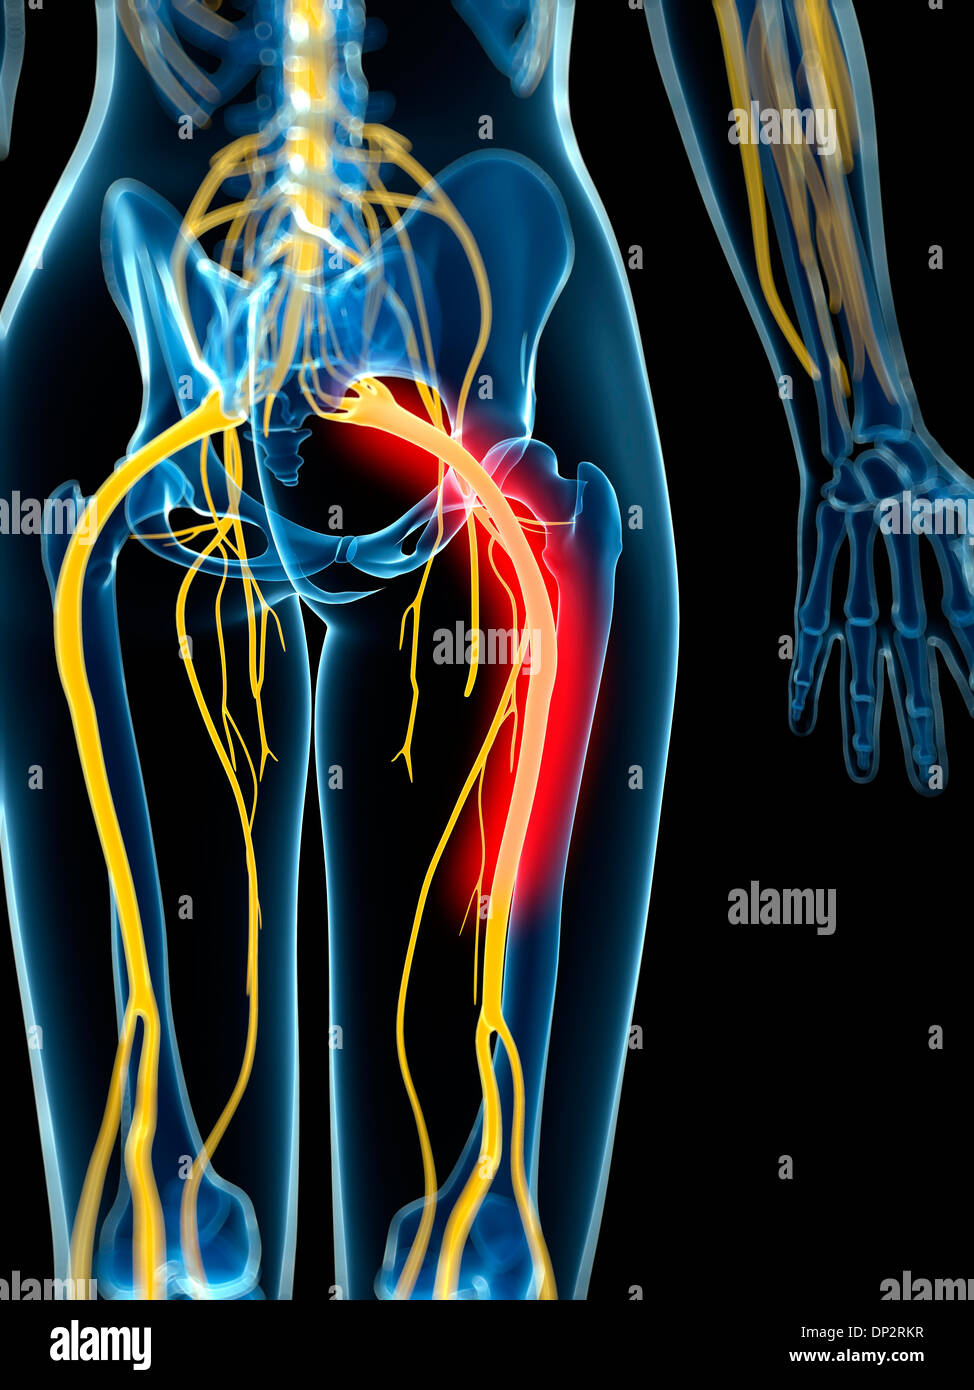

Nerf sciatique douloureux, artwork Banque D'Imageshttps://www.alamyimages.fr/image-license-details/?v=1https://www.alamyimages.fr/nerf-sciatique-douloureux-artwork-image65216027.html

Nerf sciatique douloureux, artwork Banque D'Imageshttps://www.alamyimages.fr/image-license-details/?v=1https://www.alamyimages.fr/nerf-sciatique-douloureux-artwork-image65216027.htmlRFDP2RKR–Nerf sciatique douloureux, artwork